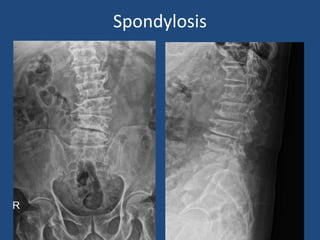

Spondylosis

Degenerative Scoliosis